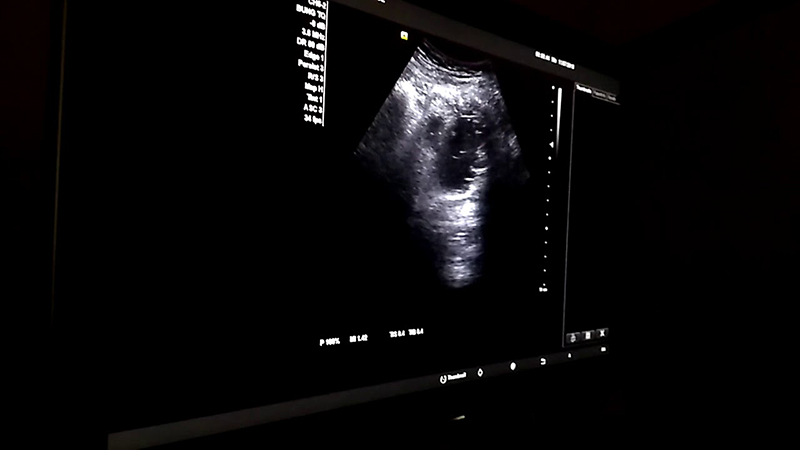

Siêu âm là một kỹ thuật hình ảnh y tế được sử dụng rộng rãi trong chăm sóc sức khỏe phụ nữ. Nó sử dụng sóng siêu âm để tạo ra hình ảnh của các cơ quan và mô trong cơ thể.

Siêu âm được sử dụng rộng rãi trong xét nghiệm thai sản để theo dõi sự phát triển của thai nhi và phát hiện các vấn đề sức khỏe. Các xét nghiệm siêu âm có thể được thực hiện trong suốt quá trình thai kỳ để đánh giá sức khỏe của thai nhi và mẹ.

Siêu âm cũng được sử dụng để chẩn đoán và theo dõi các vấn đề sức khỏe khác nhau, bao gồm các vấn đề về bàng quang, gan, thận, và buồng trứng. Nó cũng có thể được sử dụng để giúp xác định các khối u và các vấn đề khác trong cơ thể.

Trong quá trình siêu âm, bác sĩ sẽ đặt một gel dẫn truyền lên da và sử dụng một thiết bị gọi là máy siêu âm để tạo ra hình ảnh của các cơ quan và mô trong cơ thể. Quá trình này thường không đau và không gây ra bất kỳ tác dụng phụ nào.